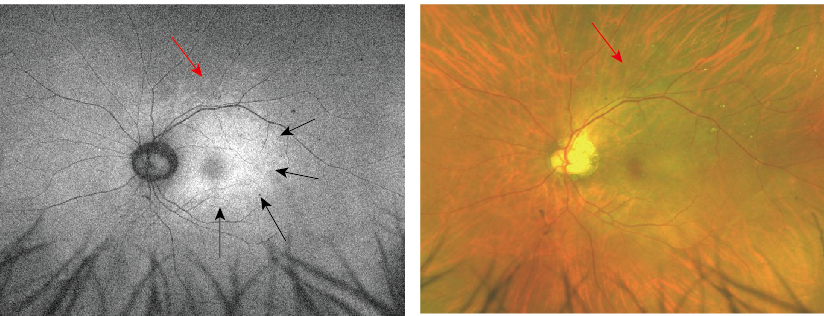

眼底自発蛍光 FAFでは乳頭から黄斑部にかけて過蛍光病変(図左、黒矢印)がみられ、またその周囲に散在する斑状過蛍光(図左、赤矢印)に一致して眼底写真でも淡い白斑(図右、赤矢印)が確認されました。